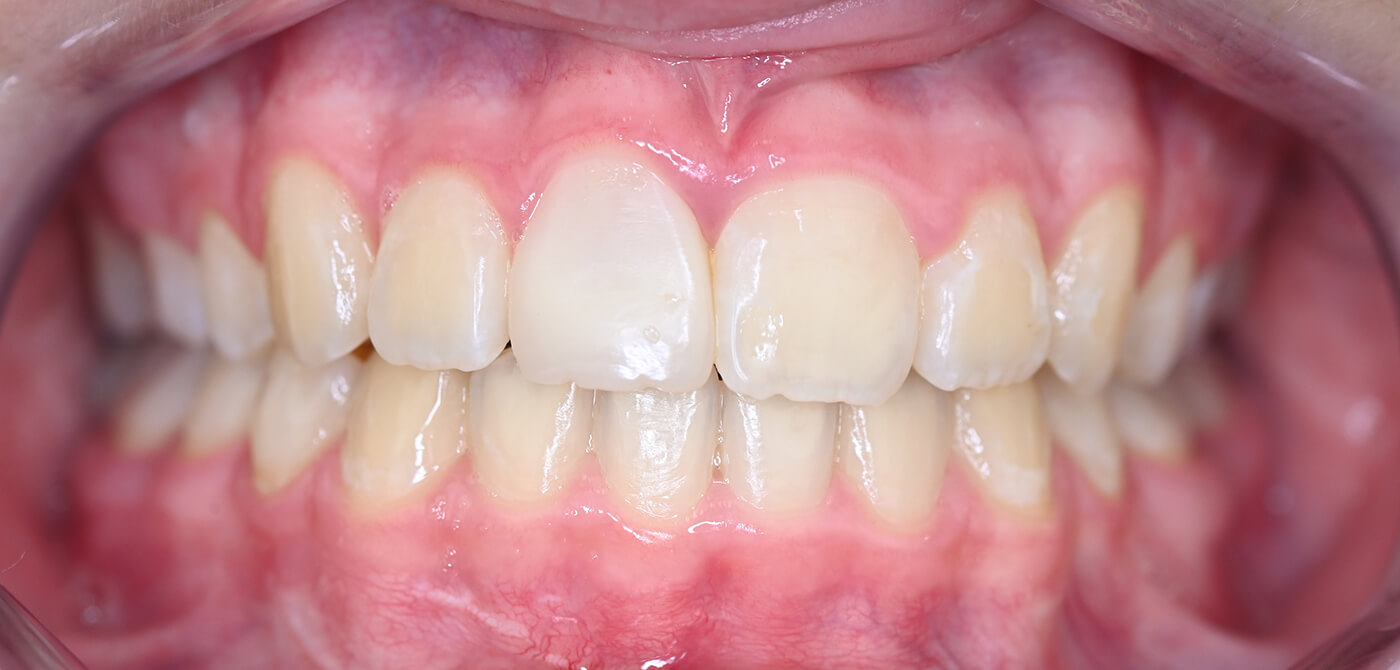

Eindresultaat

De ruimte die vrijkwam door het verwijderen van de kies is orthodontisch gesloten. Deze gelegenheid hebben we meteen benut om ook de overbeet te corrigeren. Het resultaat is een mooi en functioneel gebit, waarbij de eigen tand behouden blijft en meegroeit met de kaak.